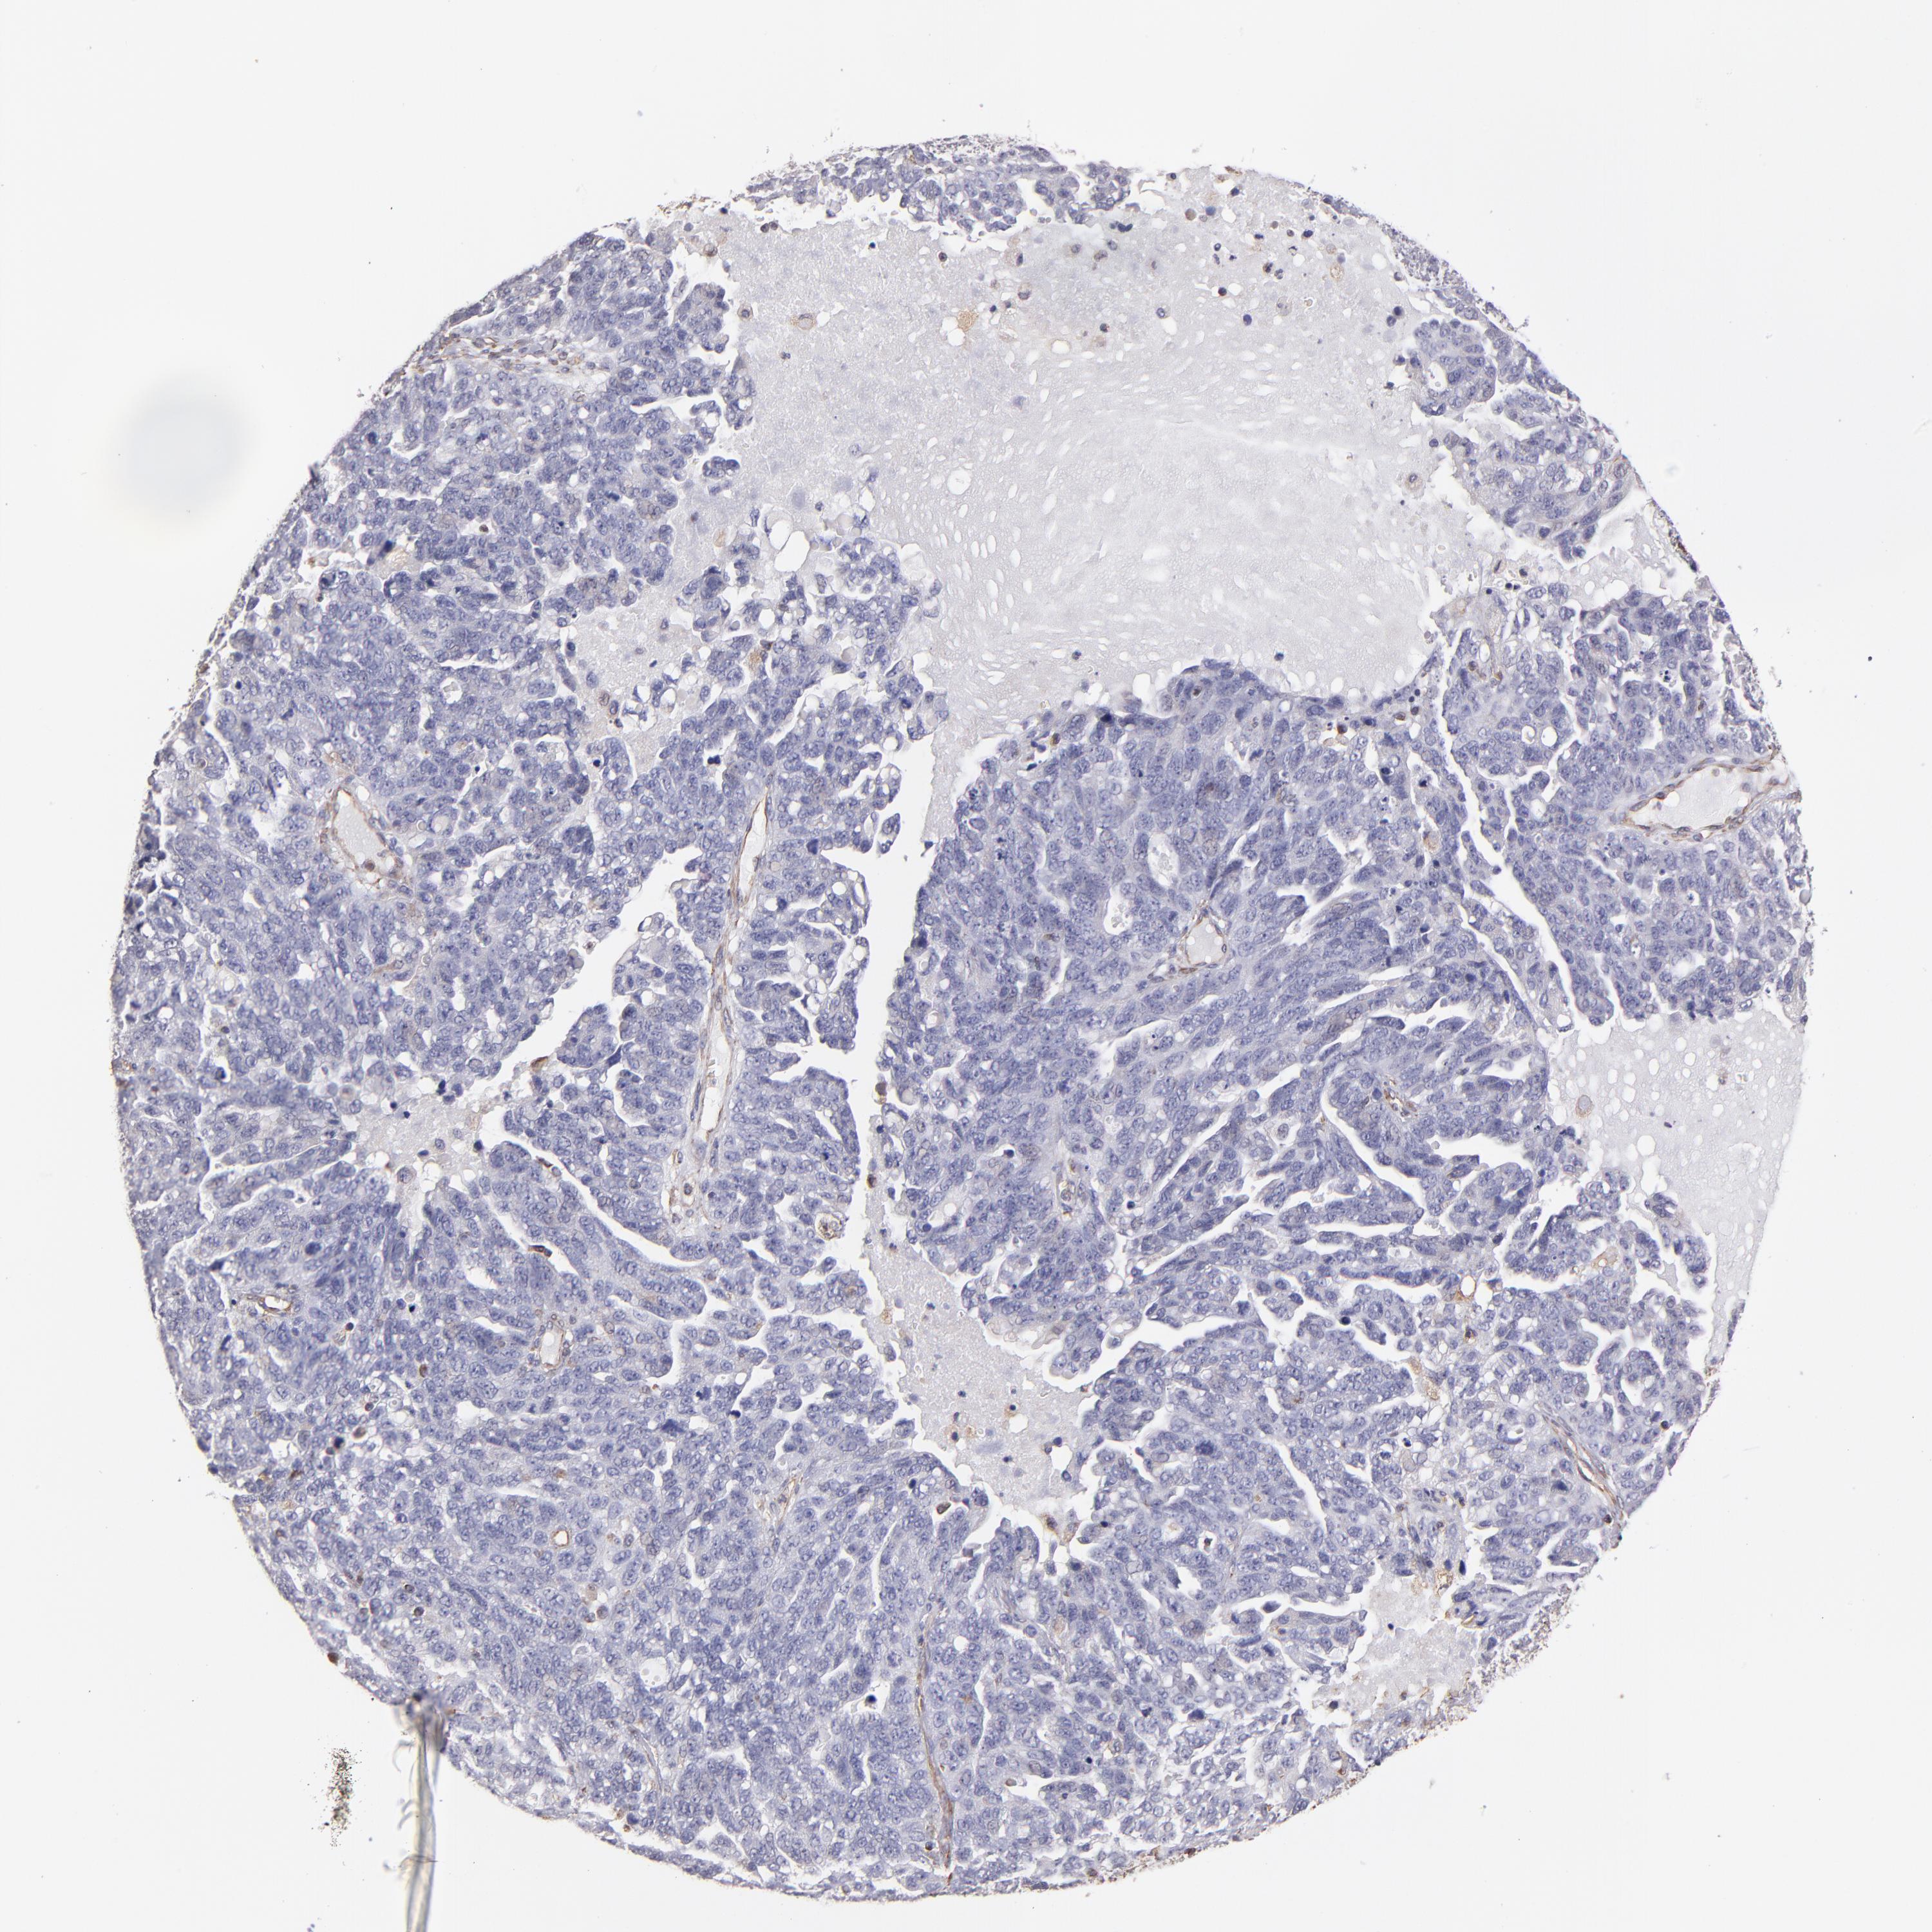

OVARIAN CANCER - Protein expressioni

A mouse-over function shows sample information and annotation data. Click on an image to view it in a full screen mode. Samples can be filtered based on level of antibody staining by selecting one or several of the following categories: high, medium, low and not detected. The assay and annotation is described here.

Note that samples used for immunohistochemistry by the Human Protein Atlas do not correspond to samples in the TCGA dataset.

Antibody stainingi

Antibody staining in the annotated cell types in the current human tissue is reported as not detected, low, medium, or high, based on conventional immunohistochemistry profiling in selected tissues. This score is based on the combination of the staining intensity and fraction of stained cells.

Each image is clickable and will lead to virtual microscopy that enables deeper exploration of all samples and also displays staining intensity scores, fraction scores and subcellular localization as well as patient and tissue information for each sample.

Antibody HPA002380

Staining

High

Medium

Low

Not detected

Intensity

Strong

Moderate

Weak

Negative

Quantity

>75%

75%-25%

<25%

None

Location

Nuclear

Cytoplasmic/membranous

Cytoplasmic/membranous,nuclear

Cystadenocarcinoma, serous, NOS

Cystadenocarcinoma, mucinous, NOS

Carcinoma, endometroid